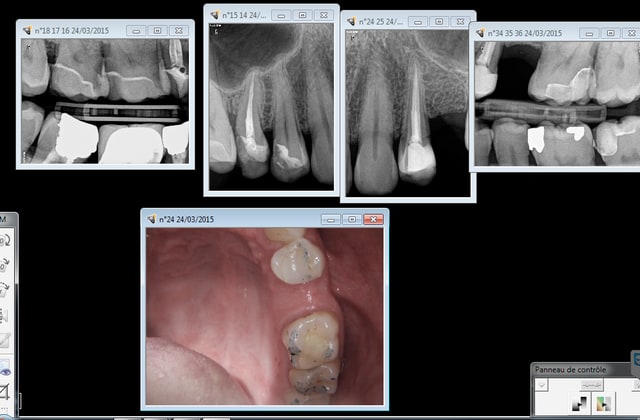

Ben justement faut pas que ca saigne. Contrairement au silicone avec lequel tu peux prendre une empreinte. Sur ce cas ca saignait grave.

Autre chose modèle positif unitaire obligatoire pour couronnes et bridges. En plus des 30 000 euros de la camera tu rajoutes 30 euros pour ces modèles.

Capture d e cran 2015 03 29 16.22 - Eugenol